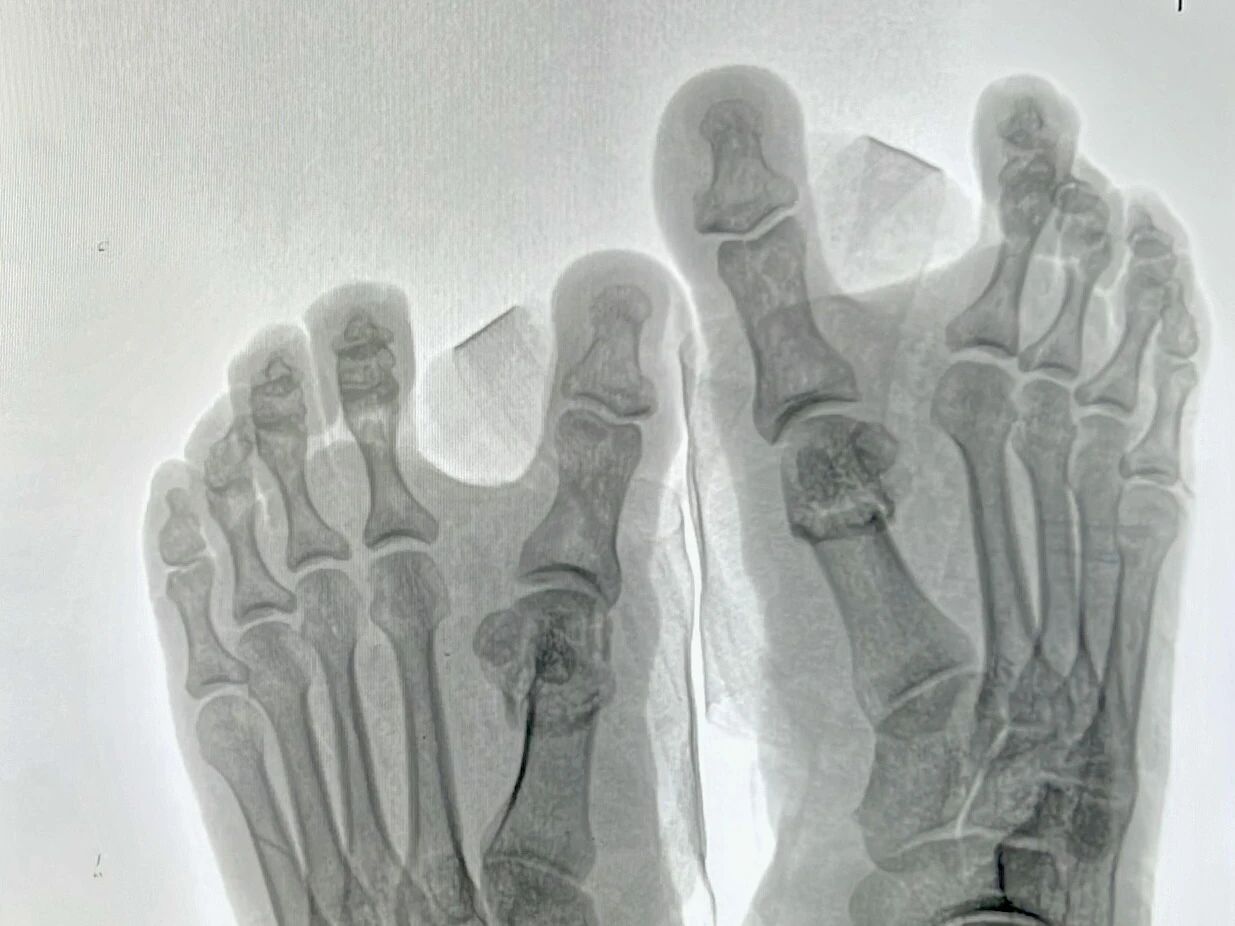

▲术后即刻行走